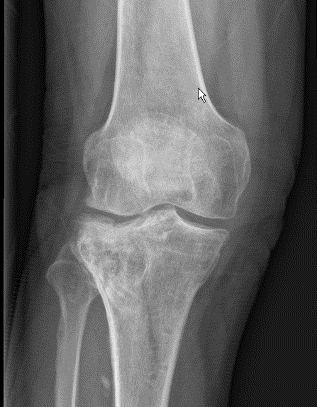

2、图3-6 术前CT见胫骨平台严重塌陷、劈裂

胫骨平台骨折的病人,如果在30年前大多数医院应该会选择保守治疗。那时CT尚未普及,而仅凭X片会低估其损伤的严重程度,容易产生可不必手术的假象,也难以准确判断骨折移位情况。即使想做手术,也没有什么好的内固定可供选用。

保守治疗肯定会遗留

膝关节功能障碍

、创伤性关节炎、跛行及畸形,造成残疾,而现在,我们采用积极的手术治疗让患者恢复了正常的外观及功能。